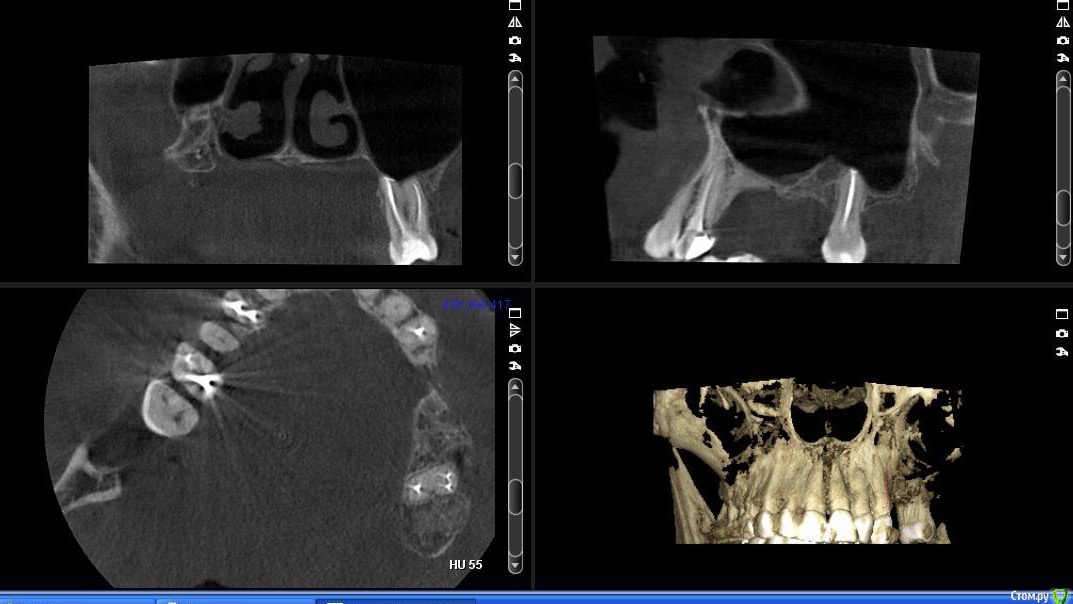

togrul Опубликовано 6 апреля, 2017 Поделиться Опубликовано 6 апреля, 2017 (изменено) Добрый день коллеги . Необходима Ваша помощь в планировании лечения. Пациентке нужно установить 2 имплантата в позиции 24-26. При анализе кт пришёл к выводу : 1 - провести НКР для восстановления высоты сеткой , через 6 месяцев установка имплантатов . 2- в области 27 зуба есть радикулярная киста , как вы считаете ее нужно убирать или нет и радикулярная ли данная киста? 3 - нужно ли проводить синус с нкр или лучше провести после НКР закрытый синус ? Буду благодарен за ответы.IMG_3292.BMPIMG_3293.BMPIMG_3294.BMP Изменено 6 апреля, 2017 пользователем togrul Ссылка на комментарий

Хью Крейн Опубликовано 6 апреля, 2017 Поделиться Опубликовано 6 апреля, 2017 Киста есть. Убирать лучше с зубом. Т.к. эндолечение вряд ли будет эффективно.Вестибулярно у зуба кости очень мало. Между кистой и верхнечелюстным синусом костная стенка есть. Синус лучше открытый,вместе с НКР. И ждать от 6 месяцев.Я бы сделал так. Ссылка на комментарий

togrul Опубликовано 6 апреля, 2017 Автор Поделиться Опубликовано 6 апреля, 2017 Спасибо за комментарий. Просматривая кт зуб 27 не вовлечен в полость кисты. Я завтра скину срезы другии, Но слизистая шнайдеровой мембраны сращена на мой взгляд с кистой . И еще один момент это рубец на границе неподвижной слизистой к подвижной. Ссылка на комментарий